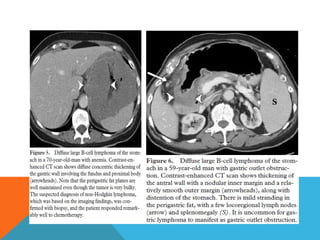

Computed tomography

Typically gastric lymphomas demonstrate marked

thickening of the stomach wall (2-4cm) with extensive

lateral extension of the tumour (i.e. along the wall of

the stomach) representing submucosal spread.

 Submucosal spread may

 Encompasses the majority of the stomach giving a

linitis plastica appearance.

 Can extend across the pylorus into the duodenum

and superiorly into the oesophagus.

 uncommon for lymphoma to result in

gastric outlet obstruction